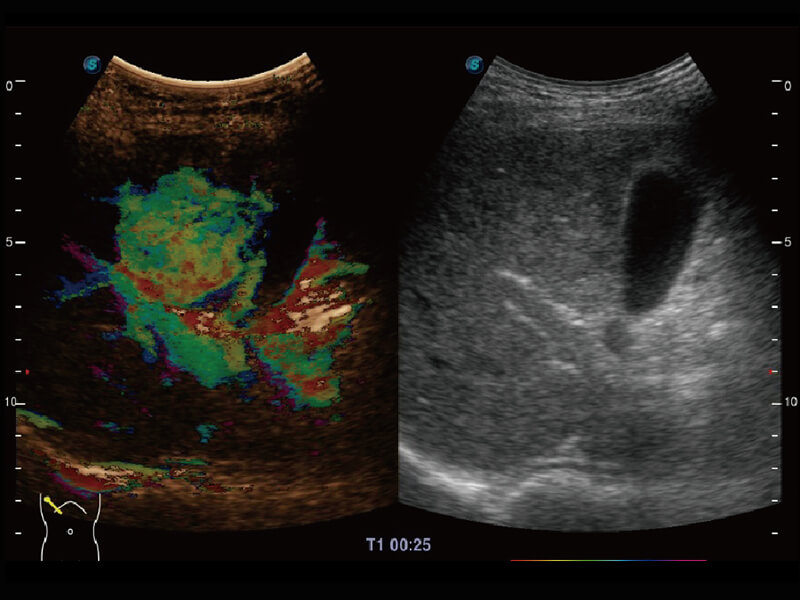

超宽频带技术,为容积成像带来优质的二维图像基础,为您呈现丰富的结构细节,栩栩如生地展示宝宝的宫内形态以及各种组织的立体结构。